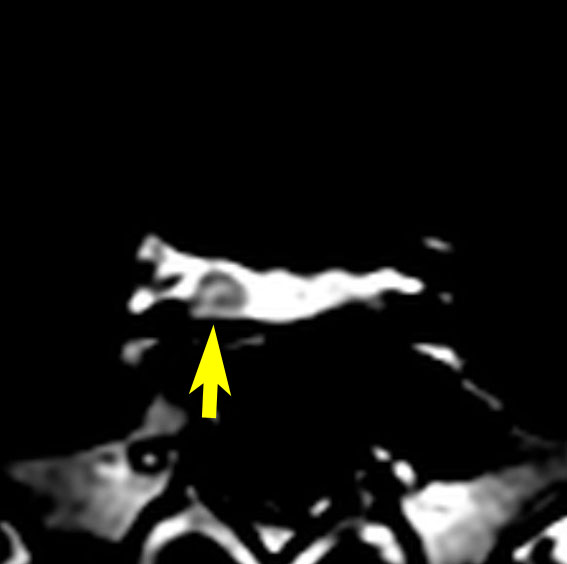

下垂体腺腫からの出血

- 下垂体腺腫からの出血はとても多いです

- 出血があるからと言って,手術しなければならないわけではありません

- 出血は自然に溶けて吸収されるので,ほっておくと小さくなります

- 出血の程度がひどくて,下垂体卒中と言われるなかでも強い症状があるときだけは手術をします

頭痛で発症して,左側の画像のような小さな腺腫が見つかりました。真っ白に見える部分は腫瘍の内部での出血です(内出血)。わずかな出血なので自然に吸収されますから,なにもしないでほっておきました。1年後に再出血(右側の画像)して,軽度の視野欠損がでました。仕方がないので手術で腺腫と出血を摘出しました。